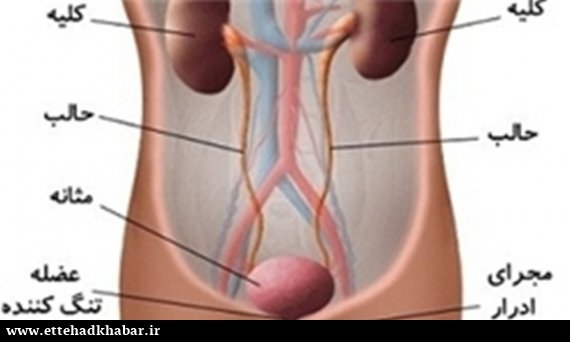

در هر ساعت کلیه های بدن انسان حدود ۷ لیتر مایع را از خون جدا می کنند این مایع را تصفیه کرده و مواد مفید و سودمند آن را به خون بازمی گردانند و مواد مضر آن را از راه میزنای به مثانه می فرستد تا دفع شوند. کجای بدنتان درد می کند مراجعه کنید آیا کلیه تان درد می کند درد کلیه در اثر عفونت کلیه یا آسیب رسیدن به آن ایجاد می شود. اما کار و وظیفه کلیه ها در بدن چیست بیا یاد بگیریم. زمانیکه کلیه ها بدرستی فعالیت کنند مواد زائد از بدن داخل ادرار ترشح می شوند همچنین کلیه ها در تنظیم سایر مواد معدنی در بدن مانند.

کلسیم و فسفر که برای تشکلی استخوان لازمند کمک می کنند مواد. کلیه ها با تولید ادارد در دفع مواد زاید تعادل الکترولیتی تنظیم هورمونی تنظیم فشار خون و هوموستازگلوکز نقش دارند. آناتومی کلیه انسان در بدن انسان به این شکل است که کلیه ها دو عضو لوبیایی شکل در دستگاه ادراری بوده و به دفع مواد زائد به صورت ادرار کمک می کنند. یکی از مهم ترین وظایفی که کلیه ها در بدن بر عهده دارند پاک کردن و تصفیه خون از زباله هاست.